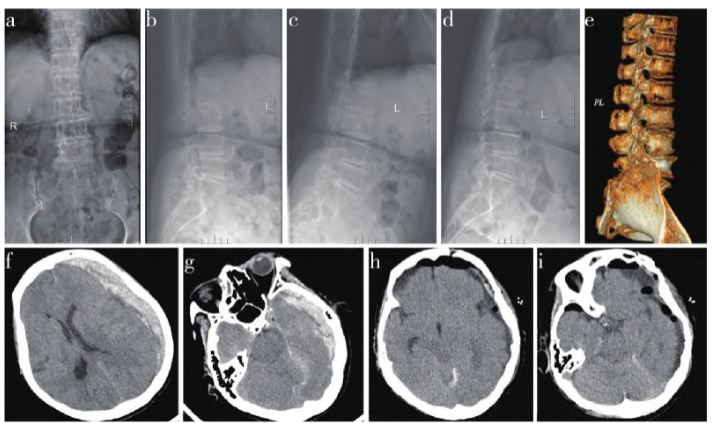

示L4/L5椎间盘突出,腰椎椎管狭窄(图1a ~ e)。术前凝血指标正常,未使用抗凝剂。于2019年7月26日行后路椎间盘切除椎间融合钉棒系统内固定术,术中见脑脊液漏,予肌肉填塞缝合修补,放置硬膜外负压引流管

,术中血压平稳;术后带管送外科重症监护病房(SICU),镇静状态下无法评估意识,术后6 h查看发现双瞳不等大,左侧直径5.0 mm无光反射,右侧直径3.5 mm光反射灵敏,停用镇静剂后患者未苏醒,负压球内见100 mL淡血性液体,复查CT示左侧额颞顶枕部新月形混杂密度影,右侧侧脑室受压,中线右偏(图1f、g),急性硬膜下血肿量约100 mL。

2019年7月26日经昆明医科大学第二附属医院神经外科会诊后急诊行左侧额颞顶急性硬膜下血肿清除术,术中见回流岩下窦静脉断裂,有活动性出血,止血清除血肿后放置硬膜外引流管;术后转入SICU。术后查体:浅昏迷,双侧瞳孔等大等圆,直径约3 mm,光反射灵敏;双上肢肌力1级,双下肢肌力0级,肌张力减低。术后第2天拔除腰椎引流管。术后第3天复查头颅CT示血肿大部分清除,颅内积气(图1h、i)。术后第6天拔除硬膜外引流管,患者气管插管拔除困难,拟行气管切开术,但家属拒绝,要求出院,失随访。

图1 病例影像学资料。a~e:术前X线片、CT示L4/L5椎间盘突出,L5椎体向前移位,L3~S1椎间隙变窄;f、g:腰椎手术后6 h CT示左侧额颞顶枕部新月形混杂密度影,右侧侧脑室受压,中线右偏;h、i:血肿清除术后3 d CT示血肿大部分清除,颅内积气